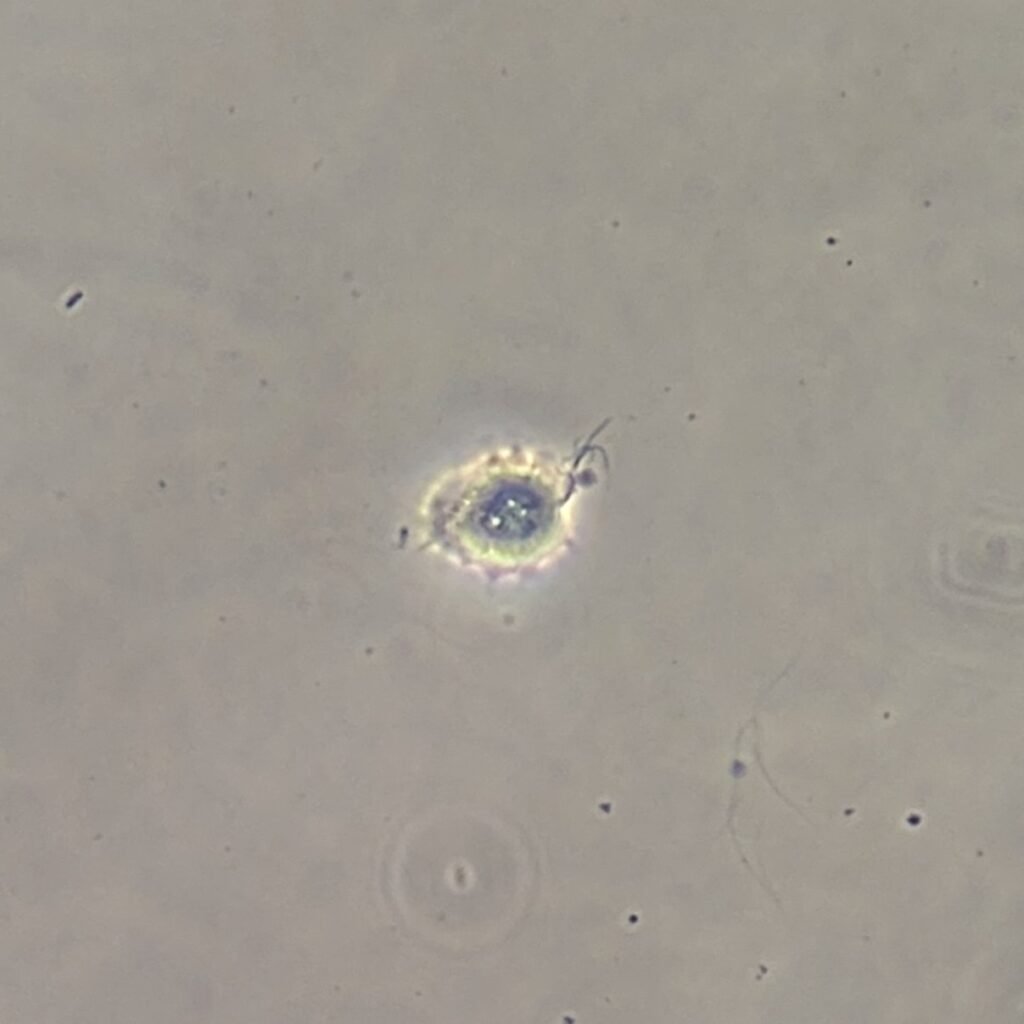

Trichomonas are pear-shaped and have four flagella. Motility is usually necessary for identification.

Trichomonas can look like a white blood cell when non-motile which is why motility is usually necessary to positively identify by microscopy.

Gallery